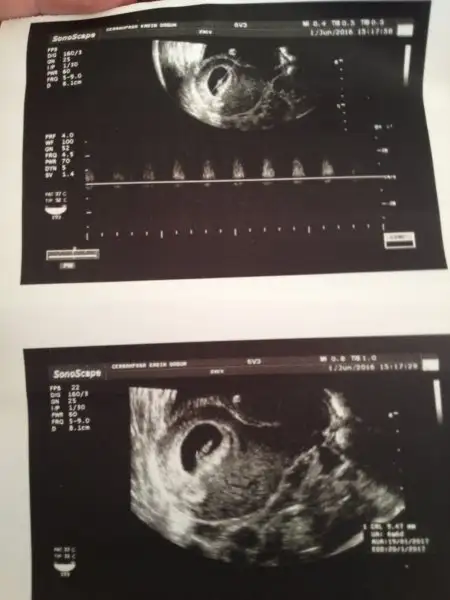

6. Hafta , 7. Hafta (ikisi de vaginal) ve 11+5 haftalık usg

yorumlarınızı heyecanla bekliyorum .

LütfenHavalianne__